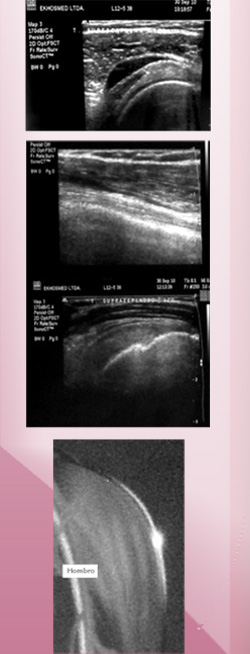

Se utiliza para evaluar estructuras superficiales del cuerpo, ya sea tendones, lesiones musculares, estudio de masas o nódulos del cuello, masas o sospecha de hernias.

Los exámenes más solicitados son las ecografías de hombro, codo y rodillas, así como también ecografía cervical.